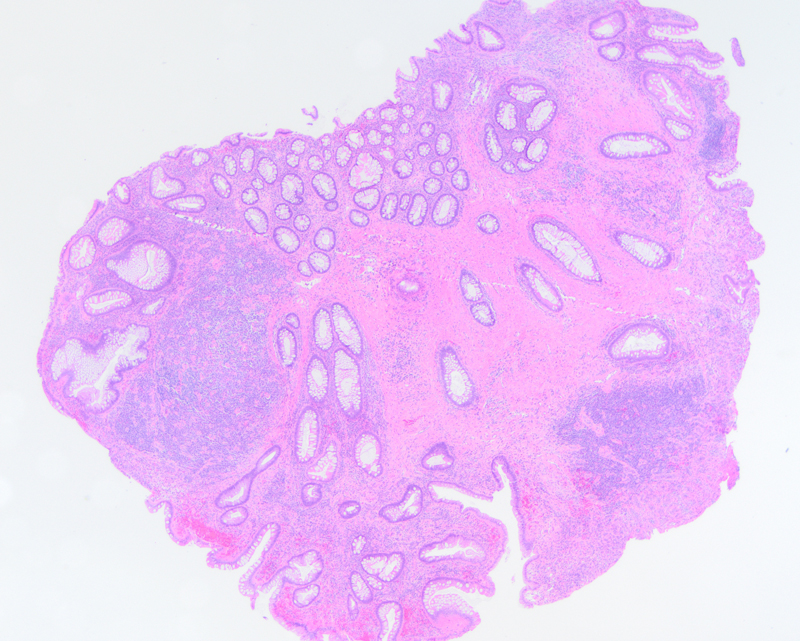

widget-ee01a79b-21f

One polyp in the stomach consisted of elongated pits lined by foveolar epithelium (Figure 1) and a second polyp had cystically dilated glands lined by parietal cells and chief cells (Figure 2). Within the transverse colon, there was a polyp with crowded crypts composed of elongated, basally oriented nuclei (Figure 3). In the ascending and sigmoid colon there were several polyps characterized by benign glands separated by unusually prominent stroma within the lamina propria (Figures 4 and 5). The sigmoid colon was notable for a polypoid lesion composed of mature adipocytes at the basal aspect of the lamina propria (Figures 6 and 7). Lastly, additional colonic polyps had proliferations of ganglion cells and spindle cells between glands within the lamina propria (Figure 8).